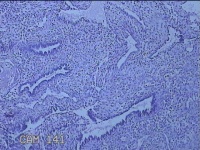

宫腔内容物

性别

女

年龄

47岁

临床诊断

1.异常子宫出血 2.慢性宫颈炎

一般病史

不规则阴道流血21天。

标本名称

大体所见

灰白暗红色不规则碎组织2.5x1.8x0.3cm一堆。

图1